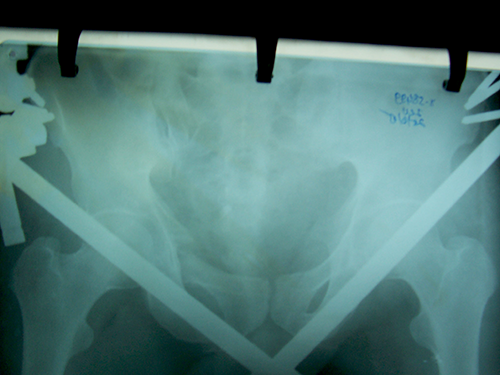

Case:8 Polytrauma

Patient having closed segmented fracture midshaft & lower 1/3 Tibia with closed fracture superior & inferior pubic rami right side with pelvis fracture following vehicular accident wastreated with intramedullary nail for fracture tibia and external fixator for fracture pelvis.

Pre-Op

Immdiate Post-op